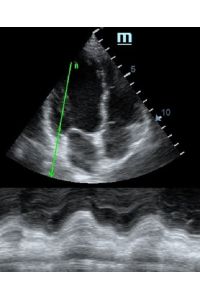

Но как же провести стандартные измерения в М-режиме, если мы его не использовали? На помощь приходит функция Free Xros M – анатомический М-режим. Имея записанную в память прибора видео петлю, мы можем провести линию М-режима в любом месте, при этом корректируя изначально не оптимальный угол.

TAPSE - показатель амплитуды движения латеральной части кольца трикуспидального клапана, позволяет количественно и быстро оценить систолическую функцию правого желудочка, норма которого составляет более 17 мм. Главным условием является проведение линии М-режима параллельно стенке правого желудочка в апикальном четырех камерном сечении, что легко достигается при Free Xros.